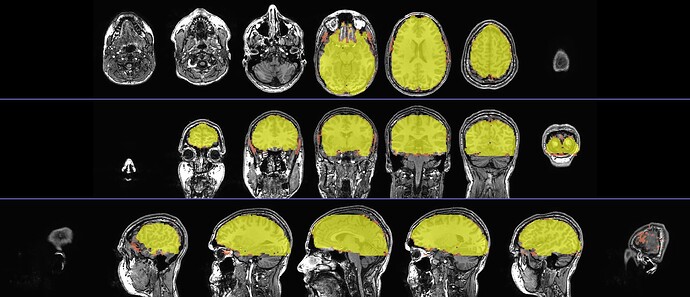

But I understand about wanting to preserve the sizes of a given row, too. If you would like to have the relative size of each panel preserved rather than stretched, you could basically ask 2dcat to pre-pad each image before gluing them together with -respad_in ...

In the example case I have made here, the pixel dimensions of the 3 images were: 3584x512 , 2614x512 and 2614x512. (I found this out by using eog .. to view them from the command line, then in the GUI viewer that pops up I right-clicked and selected "Properties" to see the image size.) So, I figured if I pre-padded each image to the dimensions of the largest, that should preserve the relative size. It is not required to be the dimensions of the largest image, I just thought that would be convenient

So, here is my command to pre-pad

2dcat                                                                        \

-nx         1                                                            \

-ny         3                                                            \

-gap        5                                                            \

-gap_col    100 100 200                                                  \

-respad_in  3584 512                                                     \

-prefix     IMG_respad.jpg                                               \

img_row.*

... which produced: